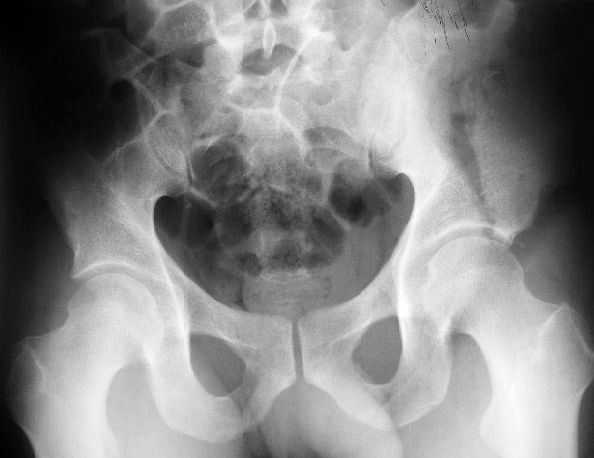

Поступил пациент после кататравмы (упал с высоты 4м). После обследования установлен Ds: Сочетанная травма. ЗТГК перелом 5-6 ребер справа. Ушиб левого леогкого. Оскольчатый перелом крыла подвздошной кости слева, со смещением. в экстренном порядке выполнена операция о/синтез таза стержневым аппаратом. Снимки прилагаются. Пациент со 2-го дня стал ходить без костылей. Из анамнеза жизни у пациента имеется гепатит В и С, с 1998г. употребляет наркотики (героин 1г в день нормальная доза). На контрольных снимках таза в аппарате смещение отломков сохраняется, да еще и стержни сломались. Подскажите ув.коллеги, как поступить в данной ситуации: оставить все как есть или добиваться репозиции в аппарате, или планировать на открытую репозицию. На сегодняшний день пациент стабилен, по анализам компенсирован. Принимает героин по другому справиться не может. С ув. Андрей

А сколько времени прошло после травмы? Аппарат лучше убрать: в таком виде он не выполняет никаких функций, а сломанные стержни скорее всего воспалятся и помешают доступу, если решите оперировать открыто. Целесообразно, как мне кажется сделать проекции Judet, чтоб определиться с линией перелома и возможным вовлечением вертлужной впадины. Вообще же лечение переломов крыла аппаратом - дело достаточно утомительное и часто неблагодарное - сложно управлять ротационным смещением и отведением/приведением фрагментов крыла, можно ухудшить стояние отломков.

Уважаемый Андрей, у пациента имеется перелом передней колонны,и после наложения аппарата положение отломков ухудшилось. возможно не из-за ваших действий а за счет тяги четырехглавой мышцы. Обе ости настойчиво будут тянуть крыло вниз.